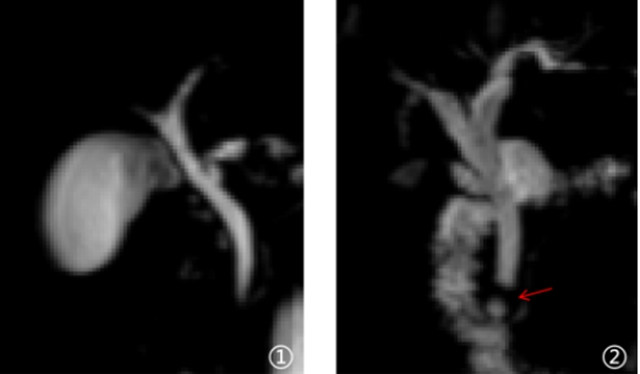

图①:MRCP显示正常胆胰管影像表现 图②:MRCP显示胆囊术后缺失,胆总管下段结石(红色箭头),以上胆管扩张